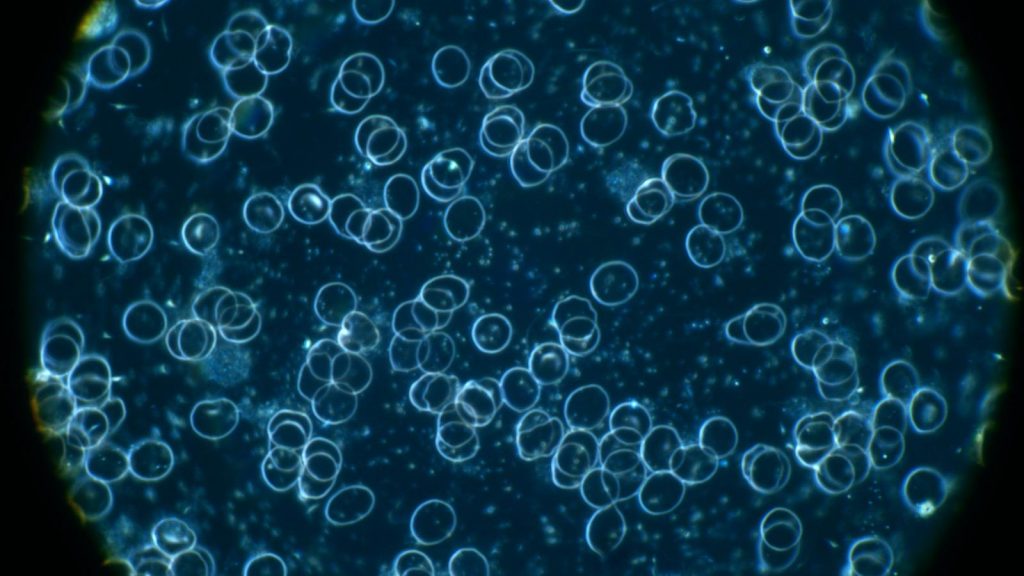

Foto: UV-Licht Mikroskop

Blutbild 2 Monate nach der Einnahme von ELENANT(R) und einer zusätzlichen Sauerstoffversorgung

Es sind einzelne Blutzellen deutlich erkennbar, es sind keine Spikes im Blut, die Belastung der Zellränder mit Fremdorganismen wird sichtbar

Aufgenommen Ende Dez 2025

Foto: UV-Licht Mikroskop

Blutbild 4 Monate nach der Einnahme von ELENANT(R) und einer zusätzlichen Sauerstoffversorgung

Es sind einzelne Blutzellen deutlich erkennbar, es sind keine Spikes im Blut, der Blick in das klare Bild ermöglicht nunmehr die Besiedlung mir Blutparasiten und Pilzen deutlich zu machen

Aufgenommen Februar 2026